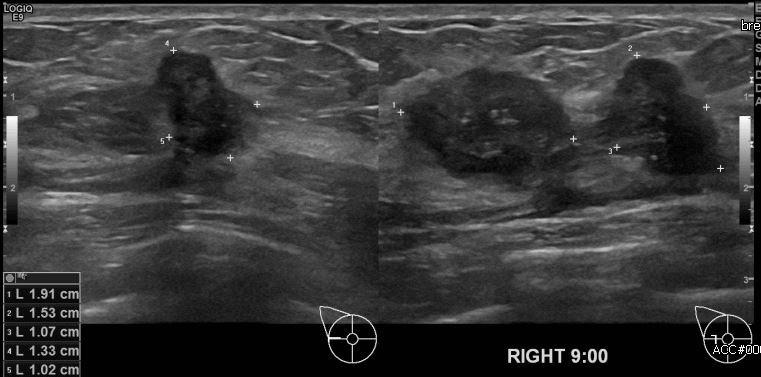

상기환자 우측 유방에 만져지는 멍울로 내원하신 40대 여성분으로 우측유방 9시

방향에 만져지는 멍울 조직검사 시행하여 우측 침윤성 유관암 진단 되었습니다.